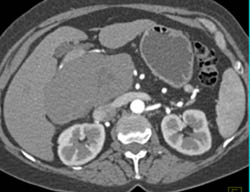

Diagnosis

Hepatoma